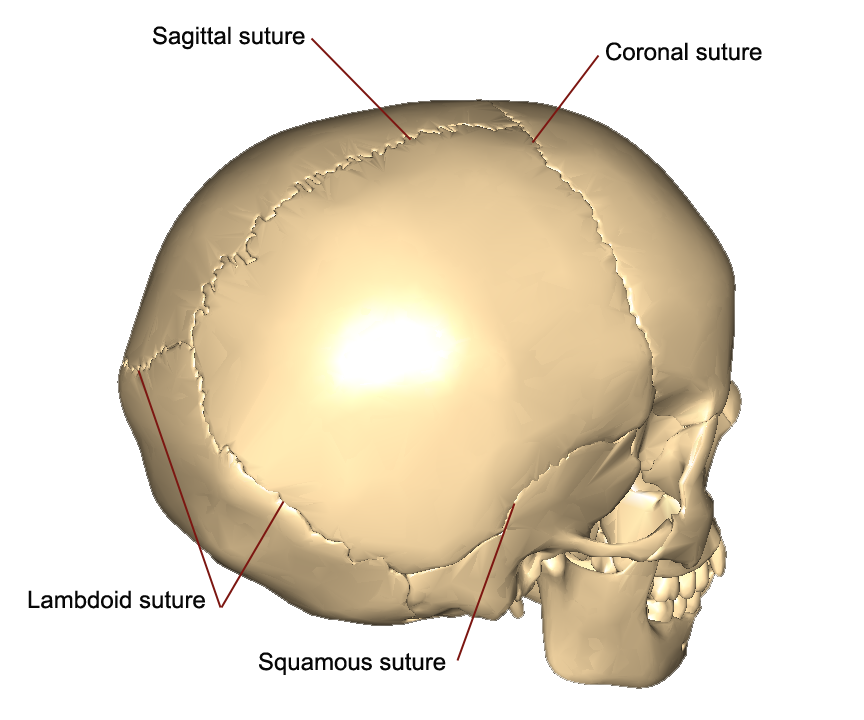

Sutures

Coronal suture - between the ___ and ___ bones

Sagittal suture - between the two ___ bones (the midline)

Squamosal suture - between the ___ and ___ bones

Lambdoidal suture - between the ___ and ___ bones

Coronal suture - between the frontal and parietal bones

Sagittal suture - between the two parietal bones (the midline)

Squamosal suture - between the temporal and parietal bones

Lambdoidal suture - between the occipital and parietal bones

Suture Junctions

Bregma - junction of the ___ and ___ sutures

Lambda - junction of the ___ and ___ sutures

Bregma - junction of the coronal and sagittal sutures

Lambda - junction of the lambdoidal and sagittal sutures